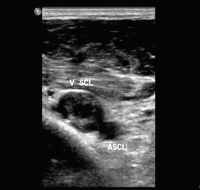

Thrombus - Vena subclavia

Abbildung 3: Thrombus in der Vena subclavia, Querschnitt.